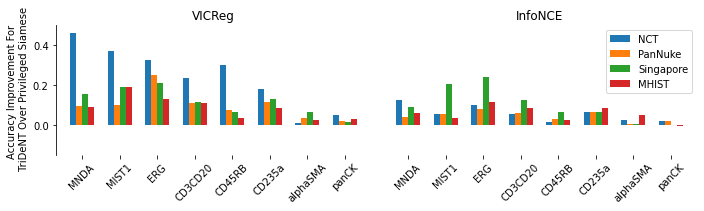

We first demonstrate that TriDeNT ♆ is highly effective for improving the quality of representations in the primary encoder by distilling privileged information from immunofluorescence (IF) images to H&E stained images (Figure 2 and Table S6). Models are trained on the SegPath dataset [22], which consists of eight subsets of H&E images paired with an image derived from the IF stain of a consecutive slice for one of eight antibodies. Evaluation is performed on four standard computational pathology tasks (see Section S2 for full details). We find that the model significantly increases performance by up to 101% compared to a privileged baseline model. TriDeNT ♆ retains not only the useful features shared between inputs, but also the features which are only present in the primary data, leading to better performance on all evaluated tasks. Even in cases where the privileged data does not appear to significantly improve performance, such as staining with CD235a, TriDeNT ♆ still achieves comparable performance, as it obtains a strong supervisory signal from the additional H&E branch. This is in contrast with the privileged Siamese setting, where it is clear that the pairing can cause a seismic drop in classification accuracy if the privileged data is not informative for the task being evaluated.

The performance of TriDeNT ♆ is noticeably more polarised for the InfoNCE loss than for the VICReg loss, as its best accuracies are higher but its performance is lower on average, despite its performance in the simple Siamese setting being higher than that of VICReg on these tasks. This could be because VICReg is explicitly designed to handle different inputs on each branch, with each representation being regularised separately, as opposed to InfoNCE which has no such process.

We see that there are significant performance gains of up to 101% (0.4566 to 0.9169, see Table S6) in the NCT tissue type classification task for TriDeNT ♆ against the baseline privileged method. Perhaps unsurprisingly given the diagnostic importance of cytokeratin stains for detecting tumours, the greatest increase – 9.0% – in performance against the unprivileged baseline method was achieved for the pan-CK model, with similar gains for SMA. Compared to the baseline unprivileged method, there was less benefit for pairing CD235a or ERG (-0.5% and +3%), perhaps because red blood cells (stained by CD235a) and the endothelium (stained by ERG) were less present in the NCT slides. Still, compared to the baseline privileged method, performance on CD235a and ERG was significantly improved, by 51% and 56% respectively.

In the PanNuke neoplastic cell detection task, we see that in Siamese models, some stains help improve prediction accuracy while others hinder it. For example, privileged Siamese training is considerably less accurate for MIST1 and ERG stains, which stain plasma and endothelial cells respectively, while it is more accurate for SMA and pan-CK, which stain smooth muscle cells/myofibroblasts and epithelial cells respectively. There is simply more semantic content in the SMA and pan-CK masks due to their lower percentage of black space, which is likely to explain this disparity. For this reason, it is difficult to draw strong conclusions about whether certain stains are more effective as privileged data than others, leaving this as an interesting avenue for future work. We also note that there are some small differences in the distributions and sample sizes of the tissue samples used for different stains, as the unprivileged models have a range of 0.0533 for their accuracies on the tissue type classification task. The differences are even less for the PanNuke neoplastic cell detection task, as these have a range of 0.0321.